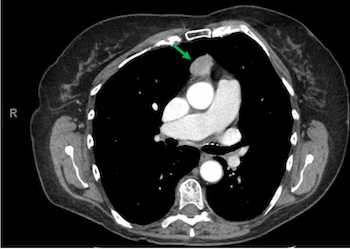

A 72-year-old female presented with a history of IDA, dyspnea, and upper GI symptoms and underwent CT imaging for evaluation of her symptoms.

Thymomas are one of the most common tumors in the anterior mediastinum in adults. About 40% of cases are associated with paraneoplastic or autoimmune syndromes. Morphologically, these are epithelial tumors with bland spindle cells with a storiform pattern. Most cases lack necrosis and have a low Ki-67 index; however, these can be seen with atypical type A thymomas. They will stain strongly for epithelial markers (p40/p63) and will usually lack TdT-positive T-cells. Complete resection associated with overall survival even though about 20% of patients will have a Masaoka stage II or III tumors.